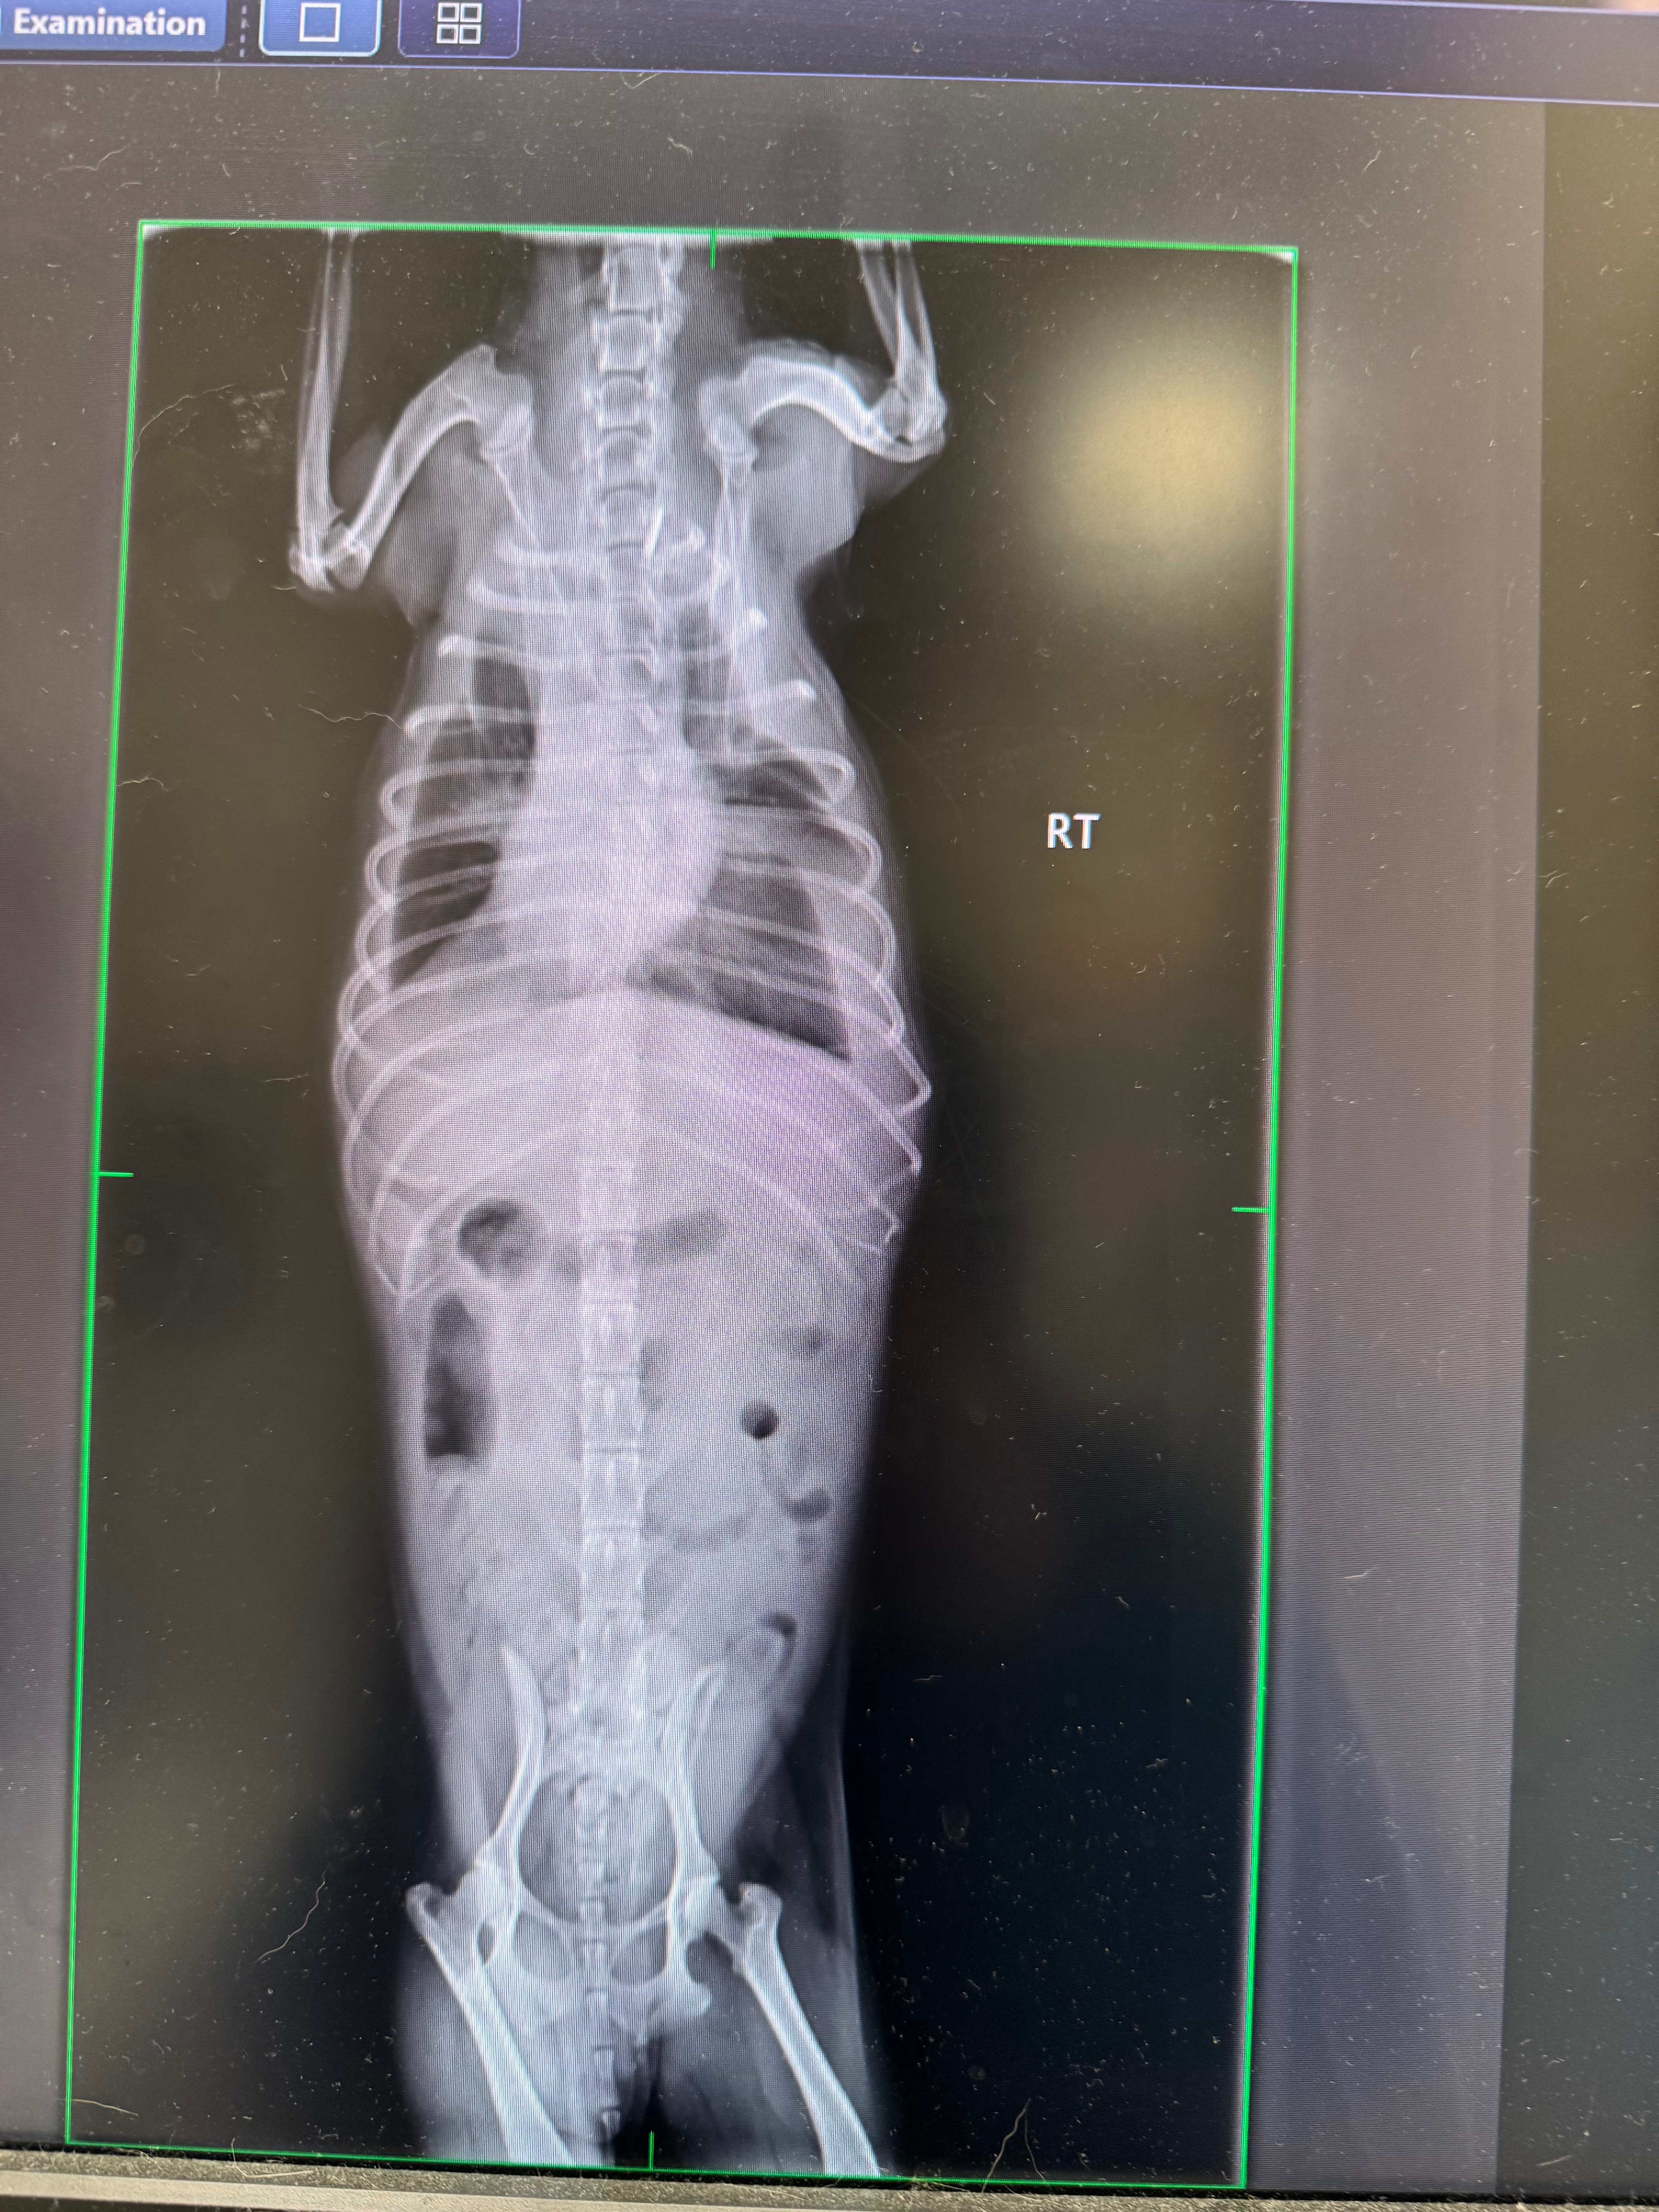

My sweet little boy, Boogie, recently had a provisional diagnosis of GI Lymphoma (a form of cancer). He’s my whole world, and I want to give him the best chance possible. We’ve already started vet care, but the cost of treatment and ongoing visits is overwhelming.